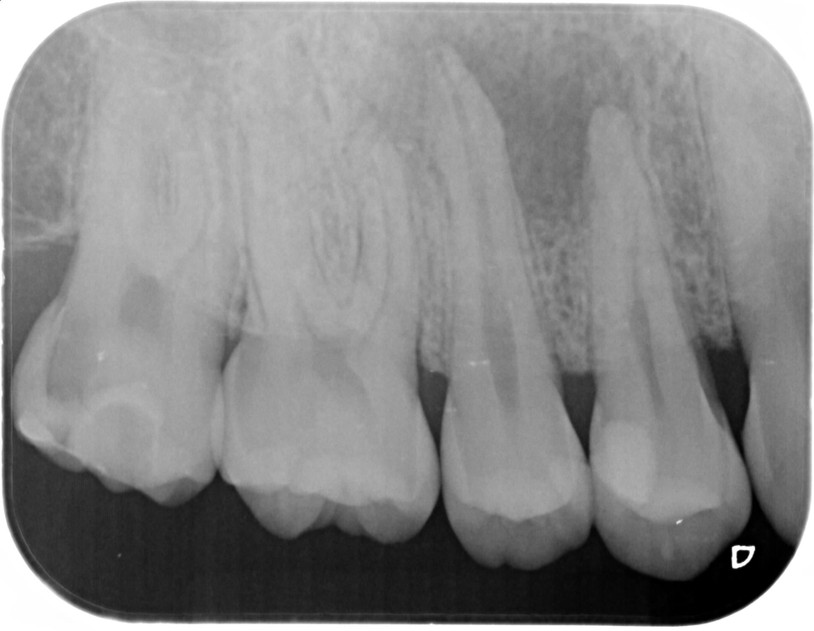

③![]() 根管治療後1年経過時 |

④![]() 根管治療後2年経過時 |

神経の治療後、①→②→③→④と時間をかけて徐々に治ってくることがあります。

神経の治療は細菌感染を除去する治療です。細菌がいなくなれば、無駄に神経をとらなくても良い歯もあるかもしれません。

| 患者様データ | 30代 男性 |

| 来院時の主訴 | 「他院で右上の歯3本とも神経をとる必要があると言われた。なんとか神経を残したい。」 |

| 術前検査結果 |

右上第一小臼歯:打診痛(+)・歯髄の生活反応有り 右上第二小臼歯:打診痛(+)・歯髄の生活反応無し 右上第二大臼歯:打診痛(ー)・歯髄の生活反応有り |

| 医院の診断 |

右上第一小臼歯:健全→術前に神経が残せる可能性のある歯と診断 右上第二小臼歯:慢性根尖性歯周炎→術前に神経が残せない歯と診断 右上第二大臼歯:無症候性可逆性歯髄炎→術前に神経が残せる可能性のある歯と診断し、術中に神経を残せると診断 |

| 通院期間 | 2年半 |

| 来院回数 | 10回(定期的なチェック含む) |

| 治療費 | 350,000円(税抜) 《内訳》 右上第二小臼歯:精密根管治療70,000円、ファイバーポストコア20,000円、セラミック治療120,000円 右上第二大臼歯:歯髄温存療法55,000円、セラミック治療85,000円 |

| リスクと副作用 | ①根管治療歯は長期的には破折するリスク ②メインテナンスが必要 |

| ココがこだわりのポイント☝ |

レントゲン検査や患者様の訴える症状だけでは神経を残せるかどうかは断定できません。 この方もレントゲン写真上では神経を残せないように見える歯でしたが、治療前に検査を入念に行うことで残せる可能性を見出すことができました。 同じ悩みを抱えた方は是非お気軽にご相談下さい。 |